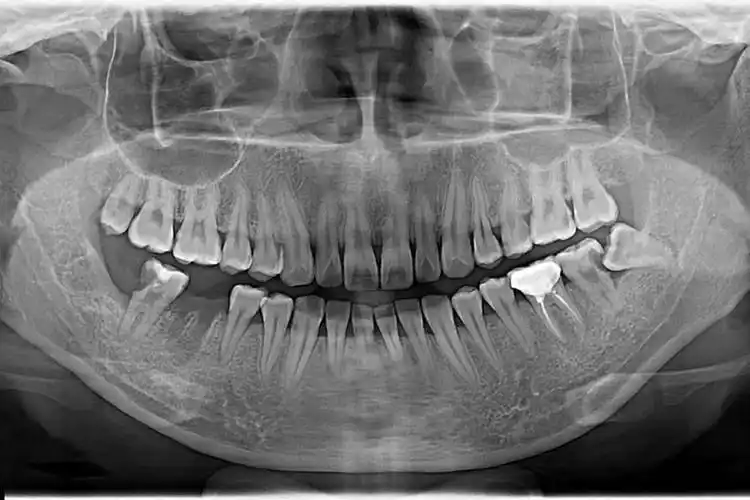

口腔全景片

x光,全景,口腔卫生,影片,牙科成像

ct检查,全景,人的嘴,x光,口腔卫生